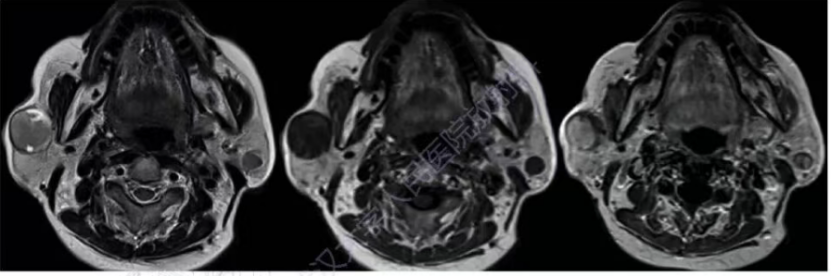

女,83岁,双侧腮腺BCA,T2WI呈中等稍高信号,右侧病灶外周见小片囊变高信号,T1WI呈低信号,增强明显强化